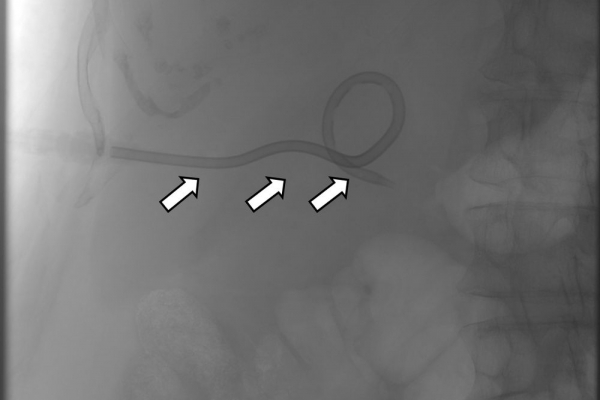

Η παροχέτευση των χοληφόρων σε αυτές τις περιπτώσεις θα πρέπει να γίνεται άμεσα, είτε ταυτόχρονα προς τα έξω και προς το 12κτυλο (έσω-έξω παροχέτευση), είτε μόνο προς τα έξω με τη βοήθεια pigtailκαθετήρα (εξωτερική παροχέτευση)

Σε περιπτώσεις όπου υπάρχει απόφραξη των χοληφόρων και ενδείκνυται η τοποθέτηση ενδοπρόθεσης (stent), τότε η βατότητα των χολαγγείων και η αντιμετώπιση του αποφρακτικού ικτέρου μπορεί να διασφαλιστεί με την τοποθέτηση ενδοπροθέσεων (stents).